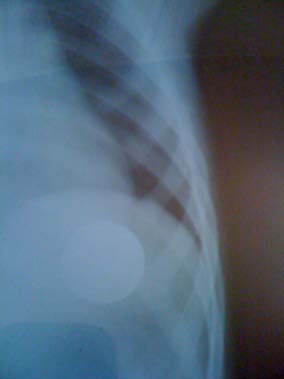

Front and side cervical radiography visualized the presence of a foreign body (coin) at the upper part of the esophagus in 28 children (80%), at the middle part of the esophagus in 05 cases (14 , 2%) and twice the foreign body was in the distal esophagus. (Fig. 2 The part was extracted on the 1 st attemptin 80.6%, on the second attemptin 11.3% and on the third attempt in 1.6% of the remaining cases. The median extraction time for the coin was 1 minute, ranging from 35 to 80 seconds, the median duration of sedation was 10 minutes. No complications related to endoscopic treatment were observed. Or even the anestheticact. All the children were monitored for 02 hours in the recovery room and redirected to the ENT service. The children whose EC was viewed at the ASP had benefited from the control ASPs performed at the ENT service, remotely from the acute episode and which showed the progression of the EC along the digestive tract until its expulsion by natural way.